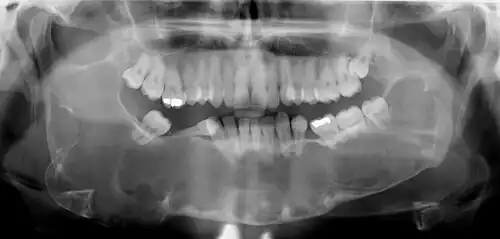

Early odontogenic keratocysts usually do not display symptoms. Typically, clinical signs and symptoms present with bony expansion, or infection. However, bony expansion is uncommon as odontogenic keratocysts grow due to increased epithelial turnover rather than osmotic pressure. When symptoms are present they usually take the form of pain, swelling and discharge due to secondary infection. Odontogenic keratocysts are usually noted as incidental radiographic findings. Radiographically they can be seen as unilocular or multilocular radiolucencies. They can be mistaken for other cysts such as residual cysts or a dentigerous cyst if they occur over an unerupted tooth.[8]

Radiographs of odontogenic keratocysts show well-defined radiolucent areas with rounded or scalloped margins which are well demarcated.[13] These areas can be multilocular or unilocular. The growth pattern of the lesion is very characteristic from which a diagnosis can be made as there is growth and spread both forward and backward along the medullary cavity with little expansion. No resorption of teeth or inferior dental canal and minimal displacement of teeth is seen. Due to lack of expansion of the odontogenic keratocyst, the lesion can be very large when radiographically discovered.[10]